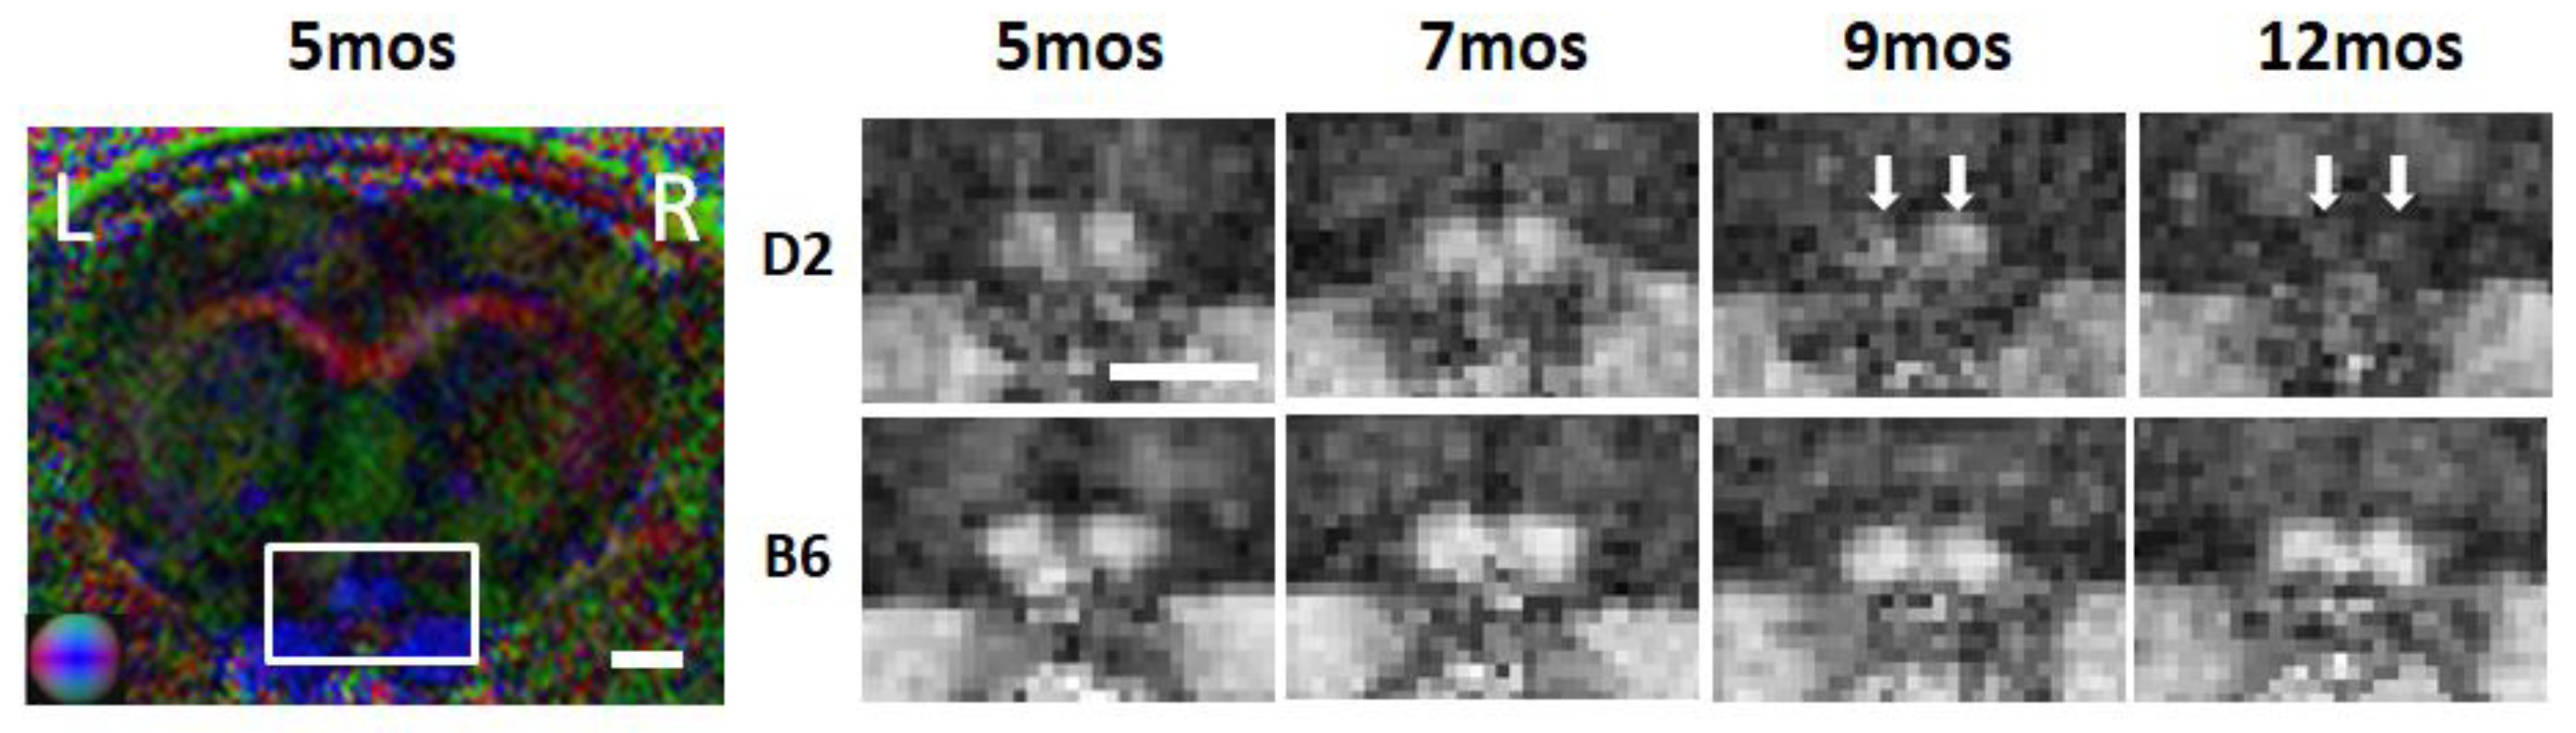

2.2. Anatomical MRI in Glaucona

- Yang, X.-L.; Van Der Merwe, Y.; Sims, J.; Parra, C.; Ho, L.C.; Schuman, J.S.; Wollstein, G.; Lathrop, K.L.; Chan, K.C. Age-related Changes in Eye, Brain and Visuomotor Behavior in the DBA/2J Mouse Model of Chronic Glaucoma. Sci. Rep. 2018, 8, 4643. [Google Scholar] [CrossRef] [PubMed]

- Fiedorowicz, M.; Wełniak-Kamińska, M.; Świątkiewicz, M.; Orzeł, J.; Chorągiewicz, T.; Toro, M.D.; Rejdak, R.; Bogorodzki, P.; Grieb, P. Changes of Ocular Dimensions as a Marker of Disease Progression in a Murine Model of Pigmentary Glaucoma. Front. Pharmacol. 2020, 11, 1377. [Google Scholar] [CrossRef] [PubMed]